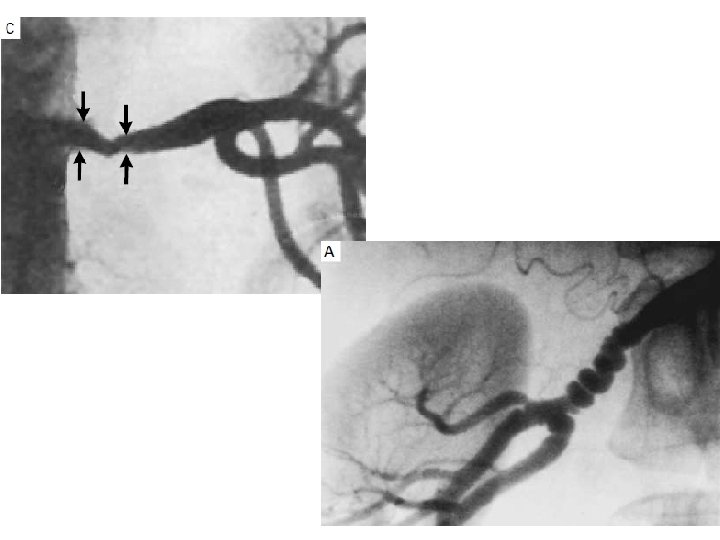

ESTENOSIS DE LA ARTERIA RENAL Se define como el estrechamiento de una o ambas arterias o sus ramas causada mas frecuentemente por aterosclerosis, menos frecuentemente por fibrodisplasia.

Aterosclerosis (ERV) • Estenosis Arteria renal Displasia Fibromuscular HIPERTENSION NEFROPATIA ISQUEMICA

El hallazgo arteriográfico de una estenosis >75% o una dilatación postestenótica del 50% sugiere la presencia de hipertensión secundaria a ERV. Sin embargo, tales hallazgos radiográficos también se pueden hallar en sujetos normotensos. La historia clínica es clave: Hipertensión severa o refractaria, Hipertensión que no responde como previamente lo hacía, Hipertensión en el contexto de un riñón atrófico, La elevación de la creatinina poco después de la institución de un IECA o un ARA II.

La estenosis de la arteria renal reduce la perfusión renal y puede llevar a: Hipertensión, Disfunción renal y/o Edema pulmonar Hasta recientemente, una estenosis arterial renal crítica se definía como una reducción del diámetro de la arteria > 50% por arteriografía. En el año 2008, la AHA definión a la ERV crítica como una reducción del diámetro de la arteria renal > 60%. Las estenosis que inducen un aumento en la secreción de renina, están asociadas con: Una caída abrupta de la filtración glomerular inducida por la inibición de la ECA (IECAs, ARA II, DRI), Atrofia renal, Bilateralidad, Compriso > 60% de la luz arterial. Rocha-sing, K. J. et al. Circulation 118, 2873– 2878 (2008)

SIGNIFICANCIA CLÍNICA DE LAS LESIONES ESTENÓTICAS Los hallazgos arteriográficos de estenosis > 75% en una o ambas arterias renales (o un 50% de estenosis en una dilatación postestenótica) sugiere que el paciente pueda presentar hipertensión renovascular. Sin embargo, estos hallazgos radiográficos pueden encontarse también en pacientes con o sin hipertensión durante la evaluación de enfermedad vascular extrarenal como hallazgos (CCG, etc).